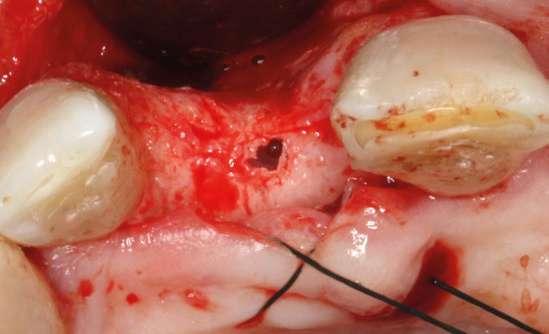

laterales se ponen de manifiesto aún más varias lesiones de esmalte que indican la parafunción en el paciente, unido a los desgastes excesivos en varias zonas (figuras 3 y 4). El paciente acude por dolor y movilidad en la pieza 11, que se ha incrementado en los últimos días, además de sensación de “diente crecido” que como podemos ver en las fotografías iniciales es real, ya que el diente se encuentra ligeramente extruido en relación con el contralateral. Estos signos parecen indicarnos una fractura o fisura. En la fotografía oclusal, podemos observar el desplazamiento del diente debido a la movilidad (figura 5). Posteriormente se realiza un sondaje positivo de la pieza, que lleva a 11 mm por lo que se confirma la sospecha de fractura y se procede a la exodoncia del diente, realizándose una regeneración posterior del alveolo con PRGF-Endoret y

esperándose 4 semanas hasta el cierre de los tejidos blandos y la neoformación ósea inicial para la colocación de un implante temprano. Cuatro semanas después, realizamos un cone-beam de control para conocer el estado del tejido óseo y poder planificar el implante. En el corte seccional observamos que se ha regenerado por completo el lecho receptor y tenemos un hueso óptimo para la inserción del implante, que por el tiempo transcurrido además es muy sencillo de expandir, con el propio implante generándose una expansión atraumática que nos permitirá ganar anchura ósea y con un implante estrecho de 3,5 mm de diámetro logramos posicionarlo sin dañar la desembocadura del nervio incisivo (figura 6). En cuanto a la longitud, con 7,5 es suficiente, no necesitándose un tamaño mayor para un correcto rendimiento biomecánico posterior.

Colocamos el implante generándose una ligera expansión vestibular, como mostramos en las imágenes intraoperatorias, para posteriormente ser sobrecorregido con hueso autólogo obtenido del fresado, embebido en PRGF-endoret y lograr una mayor anchura vestíbulo-lingual en la zona de colocación del im-

plante, clave para lograr una mejor estética y además un mantenimiento de los tejidos periimplantarios a largo plazo. En la fase quirúrgica colocamos además el transepitelial unitario para la realización de la carga inmediata y la colcación de un provisional atornillado horas después de la cirugía (figuras 7-14).

Figuras 7 y 8. Perforación inicial y colocación del implante expandiendo la zona vestibular.

Figuras 9 y 10. Visión vestibular tras la inserción del implante y colocación del transepitelial unitario para comenzar la carga inmediata.

Figuras 11 y 12. Sobre-corrección vestibular y cierre primario de los tejidos con un monofilamento no reabsorbible alrededor de la tapa de protección del transepitelial.